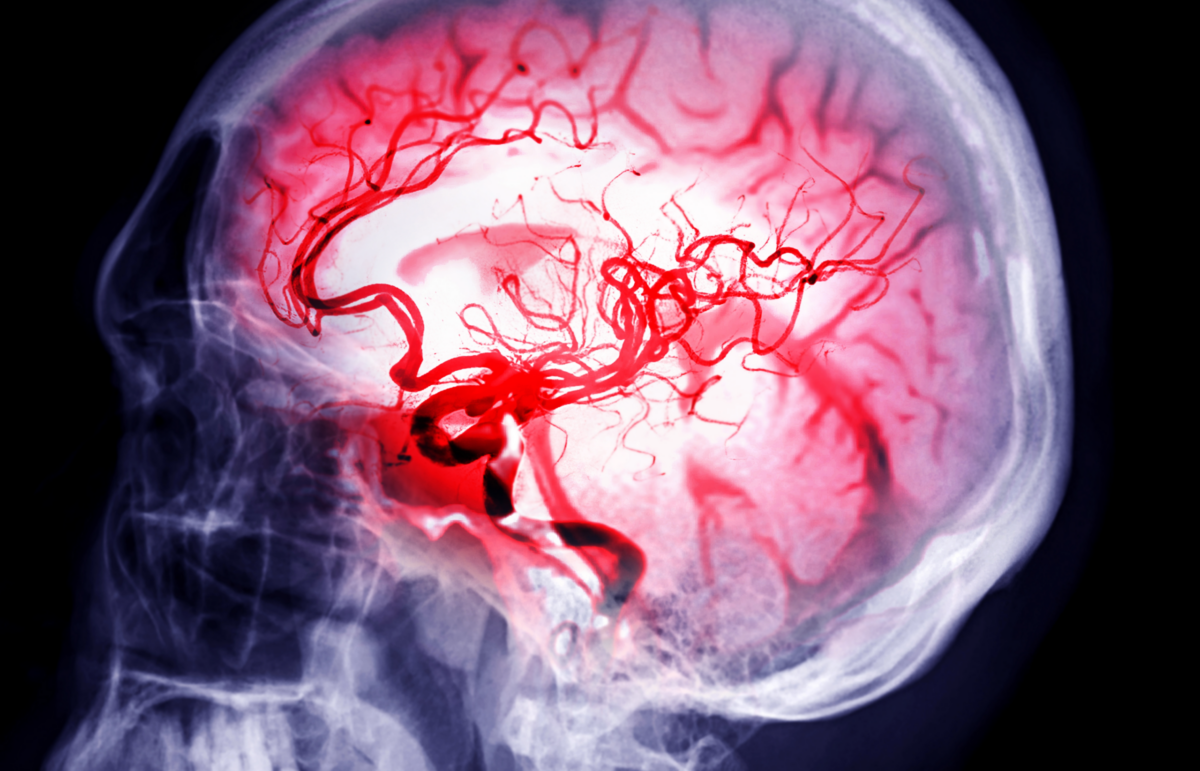

New training is set to help healthcare providers with the Richmond Ambulance Aut [...]

Richmond Ambulance Authority Looks to Diagnose Stroke Patients More Quickly Thro [...]